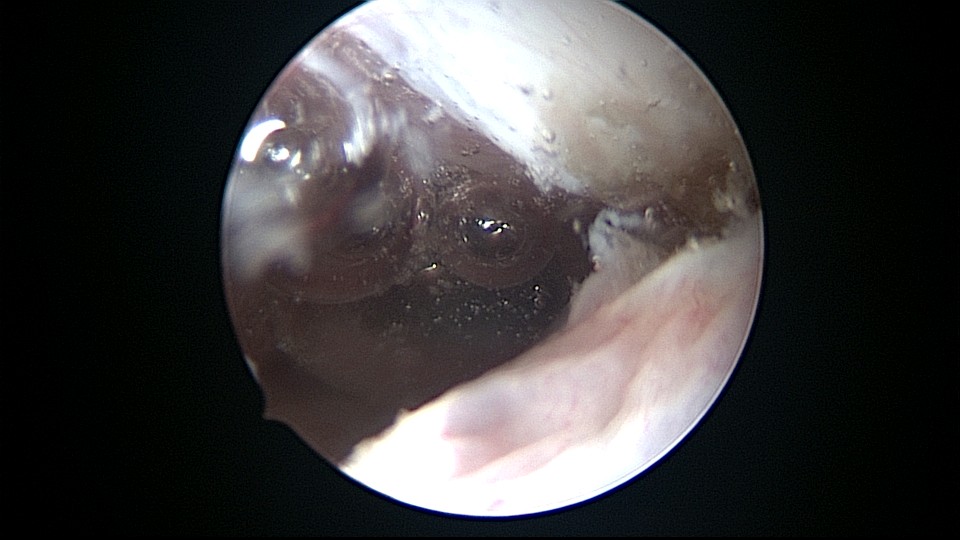

患者32岁,G2P0,自然流产2次,外院行清宫术,术后月经量减少一半。2019年6月市妇幼分粘,术后月经无改善,宫腔粘连复发,2020年11月宫腔镜探查,宫腔中上段幕状粘连,形成两个假的输卵管开口,双极电针分粘,恢复宫腔形态,显露正常的输卵管开口。2020年12月宫腔镜二探取球囊,宫腔形态正常,双侧输卵管开口可见,内膜充血。2022年5月自然妊娠,2023年1月剖宫产分娩一女婴(37+2)。现37岁,G3P1。